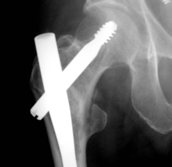

Typische pertrochantäre Femurfraktur

Die Fraktur ist schlecht reponiert und der Schenkelhals

verdreht, der Winkel des Nagels ist zu steil